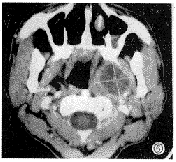

腮腺内良性肿瘤 59例混合瘤、单发腺瘤、腺淋巴瘤中49例表现为圆形、类圆形肿块,边缘清晰,密度均匀,平扫CT值20~45HU,增强扫描CT值55~88HU之间(图1);CTS表现腺内园形,边缘清晰的低密度肿块,与高密度的正常组织分界清晰(图2),病灶直径小于3cm;另10例病灶直径大于3cm,其内密度不均匀,可见单个或多个大小不等的低密度灶,病灶边缘清晰,周围肌肉、血管虽然受压移位,但脂肪间隙清晰(图3)。3例腺淋巴瘤呈囊性,CT值20~35HU之间,增强扫描病灶无强化,但壁稍强化;2例上皮病表现为腺内局限性高密度区,边缘欠清晰,与局限性炎性病变难以区分;3例血管瘤中,有1例平扫可见沙粒大小的高密度影,手术结果为结石,增强扫描表现为病灶内条状或团状高密度强化影;3例炎性假瘤边缘1例清晰2例欠清晰,CT值接近肿瘤,CTS除显示低密度充盈缺损外,也可见周围组织显影不全,腺体密度不均匀。

图1 腮腺混和瘤,病灶位于浅叶,密度均匀,边缘清晰。

图2 腺淋巴瘤,CTS示边缘清晰的充盈缺损,充盈良好的腺体组织包绕大部分病灶。

图3 腮腺混合瘤伸至咽旁间隙,但与咽侧壁间有一条脂肪间隙,病灶部分坏死,镜下见细胞增生活跃。